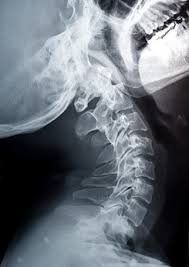

Ο λαιμός έχει μια σειρά από ζεύγη αρθρώσεων, που ονομάζονται ζυγοαποφυσιακές αρθρώσεις, και διατρέχουν προς τα πάνω και προς τα κάτω κάθε του πλευρά. Κάθε μία από αυτές είναι γεμάτη με υγρό και περιβάλλεται από μία κάψουλα. «Οταν κάποιος λυγίζει τον λαιμό του, η κάψουλα που περιβάλλει κάθε άρθρωση τεντώνεται», λέει ο Βίσκο. «Αυτό μειώνει την πίεση που ασκείται στο υγρό μέσα στην άρθρωση». Οσο πιο μικρή η πίεση που ασκείται πάνω στο υγρό, τόσο περισσότερο πλησιάζει και η αλλαγή φάσης από υγρό σε αέριο. Αυτό ονομάζεται βρασμός», λέει ο δρ Βίσκο. «Ενας άλλος όρος γι’ αυτό το φαινόμενο είναι η σπηλαίωση».